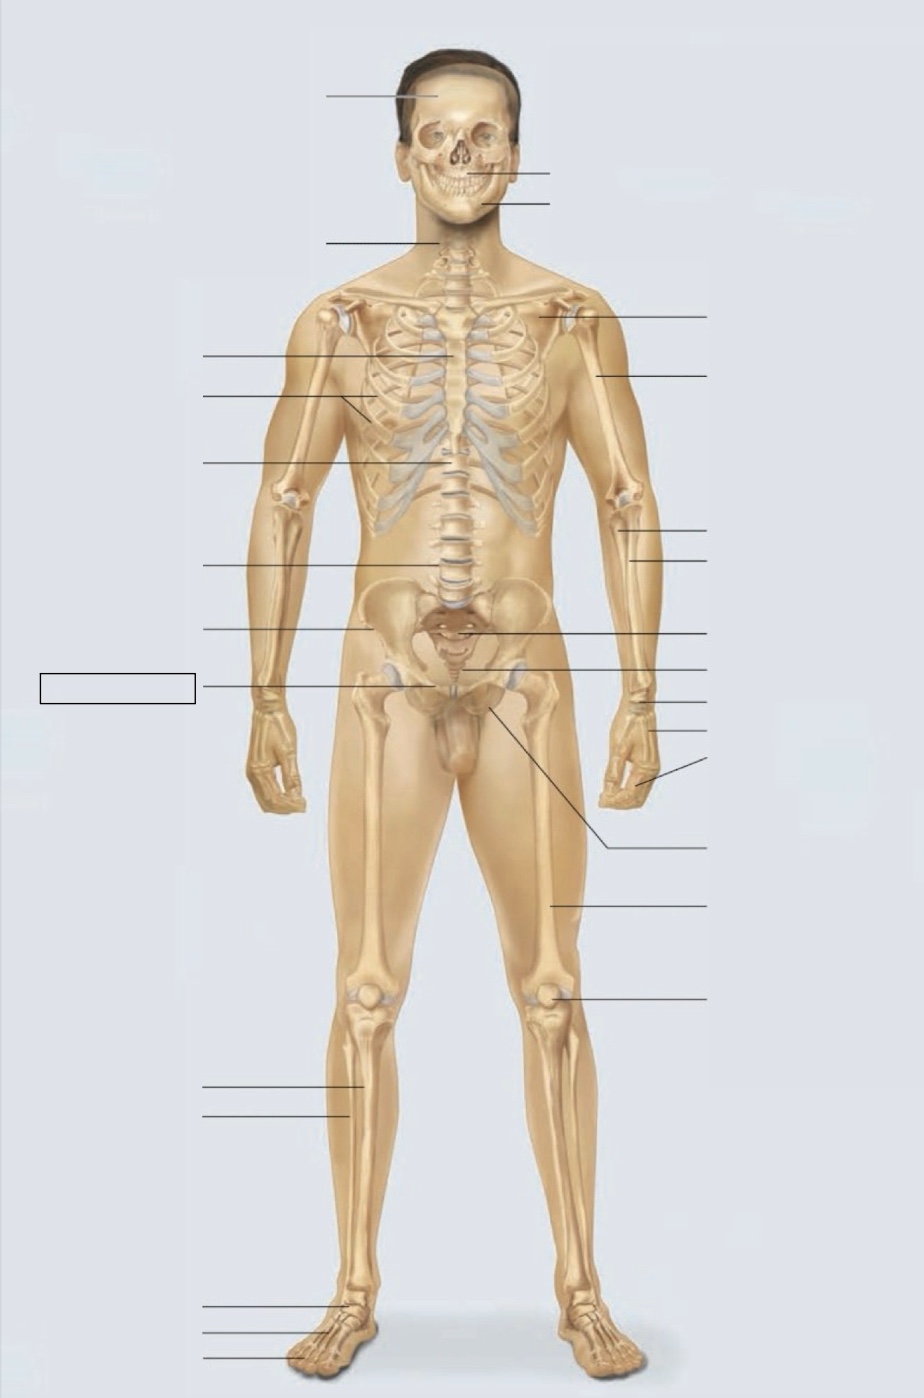

maxilla

mandible

scapula

humerus

ulna

radius

sacrum

coccyx

carpals

metacarpals

phalanges

ischium

femur

patella

phalanges

metatarsals

tarsals

fibula

tibia

pubis

ilium

lumbar vertebrae (L4)

thoracic vertebrae (T11)

ribs

sternum

cervical vertebrae

skull